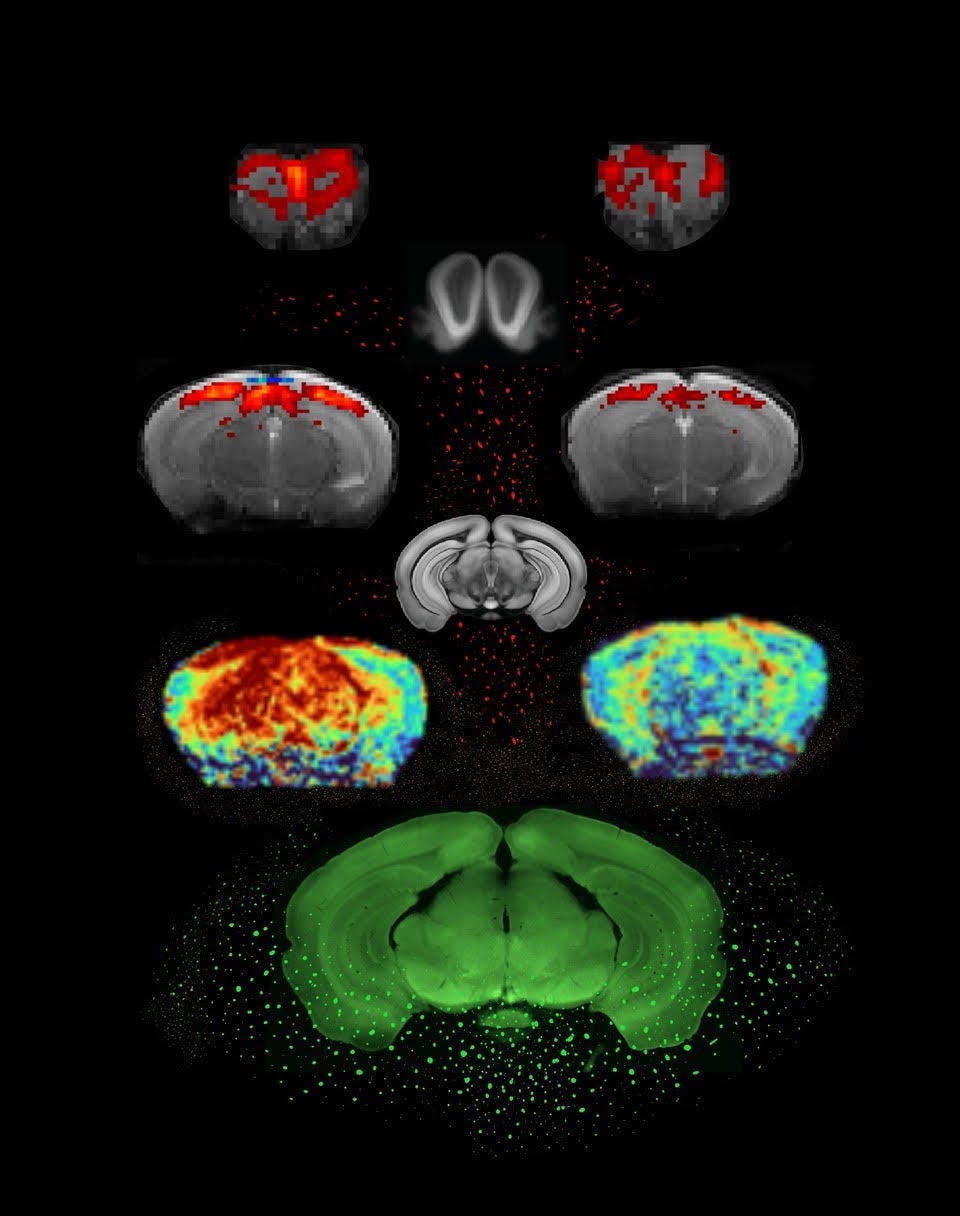

Utilizando un escáner de resonancia magnética experimental de campo ultraalto instalado en el laboratorio de Shemesh, los investigadores sometieron un modelo murino de párkinson a una técnica llamada resonancia magnética funcional (fMRI). Para dar una idea de la potencia de la máquina experimental, esta genera un campo magnético de 9,4 teslas (mientras que las máquinas médicas suelen alcanzar solo 3 teslas). Esto mejora sustancialmente las imágenes y permite una visión nítida de las estructuras cerebrales en el pequeño cerebro del ratón.

La resonancia magnética funcional se utiliza para observar qué áreas del cerebro animal (o humano) se activan en determinadas condiciones; en este caso, al exponerse a olores o estímulos visuales. En las imágenes cerebrales completas obtenidas, las áreas se iluminan en respuesta a la estimulación debido a cambios en el flujo sanguíneo y la oxigenación, impulsados por la actividad neuronal.

Los investigadores comenzaron comparando, mediante resonancias magnéticas funcionales (fMRI), la actividad cerebral de ratones vivos que producían ovillos de alfa-sinucleína con la de sus hermanos que no los producían. Los ratones tenían alrededor de nueve meses de edad, equivalente a una etapa intermedia del desarrollo de la EP.

Y, de hecho, los principales análisis, realizados por Francisca Fernandes, coprimera autora del estudio, mostraron que los ratones de control tenían una actividad normal en las áreas cerebrales correspondientes, mientras que en los ratones parkinsonianos había mucha menos actividad.

La coautora Sara Monteiro evaluó las propiedades vasculares con un método llamado «mapeo del flujo sanguíneo cerebral« y demostró que los efectos vasculares eran, de hecho, más débiles en los ratones con párkinson que en los controles.

Paralelamente, Lungu midió las contribuciones neuronales mediante una proteína llamada C-FOS, que se libera cuando se activa una neurona. Al cuantificar la cantidad de esta proteína presente en el cerebro de los ratones con EP (post mortem), descubrió que la reducción de la actividad neuronal era incluso más pronunciada que la del flujo vascular. «Concluimos que, si bien existen efectos tanto neuronales como vasculares, los cambios observados en las resonancias magnéticas funcionales se debieron principalmente a efectos neuronales», afirma Shemesh. «Las neuronas de los ratones simplemente se activaban menos».